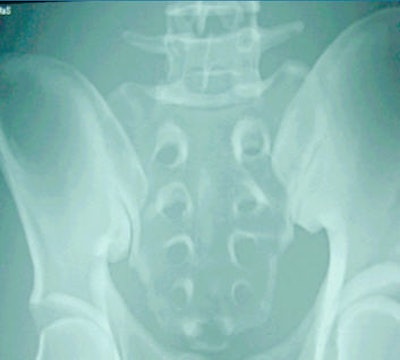

| The image above is from a CR system; the image below is from a DR system before standardizing the images. The pelvis phantom was imaged at a surface-to-image distance (SID) of 40 inches (100 cm), 80 kVp, and 50 mAs. Image courtesy of Larry Frederick and David Piazzo. |